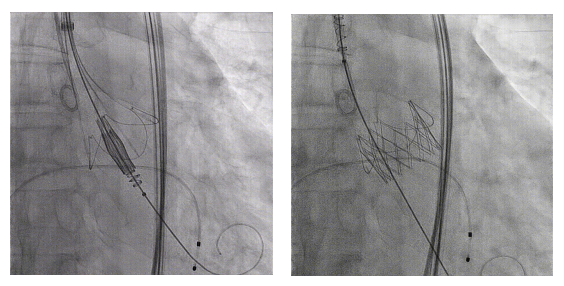

蒋路平教授团队立即启动多学科协作,联合麻醉科、超声医学科、胸外科、呼吸科等进行周密术前论证,反复优化手术路径、释放策略与应急预案。手术在全麻下进行,团队经患者大腿根部的股动脉建立通道,在DSA 实时引导下,将介入瓣膜精准输送至心脏主动脉瓣区并平稳释放。整个手术过程流畅,仅用时约 1 小时。术后心脏超声即刻显示:瓣膜位置理想、功能良好,主动脉瓣反流得到显著纠正,患者生命体征平稳。

瓣膜释放 术后造影